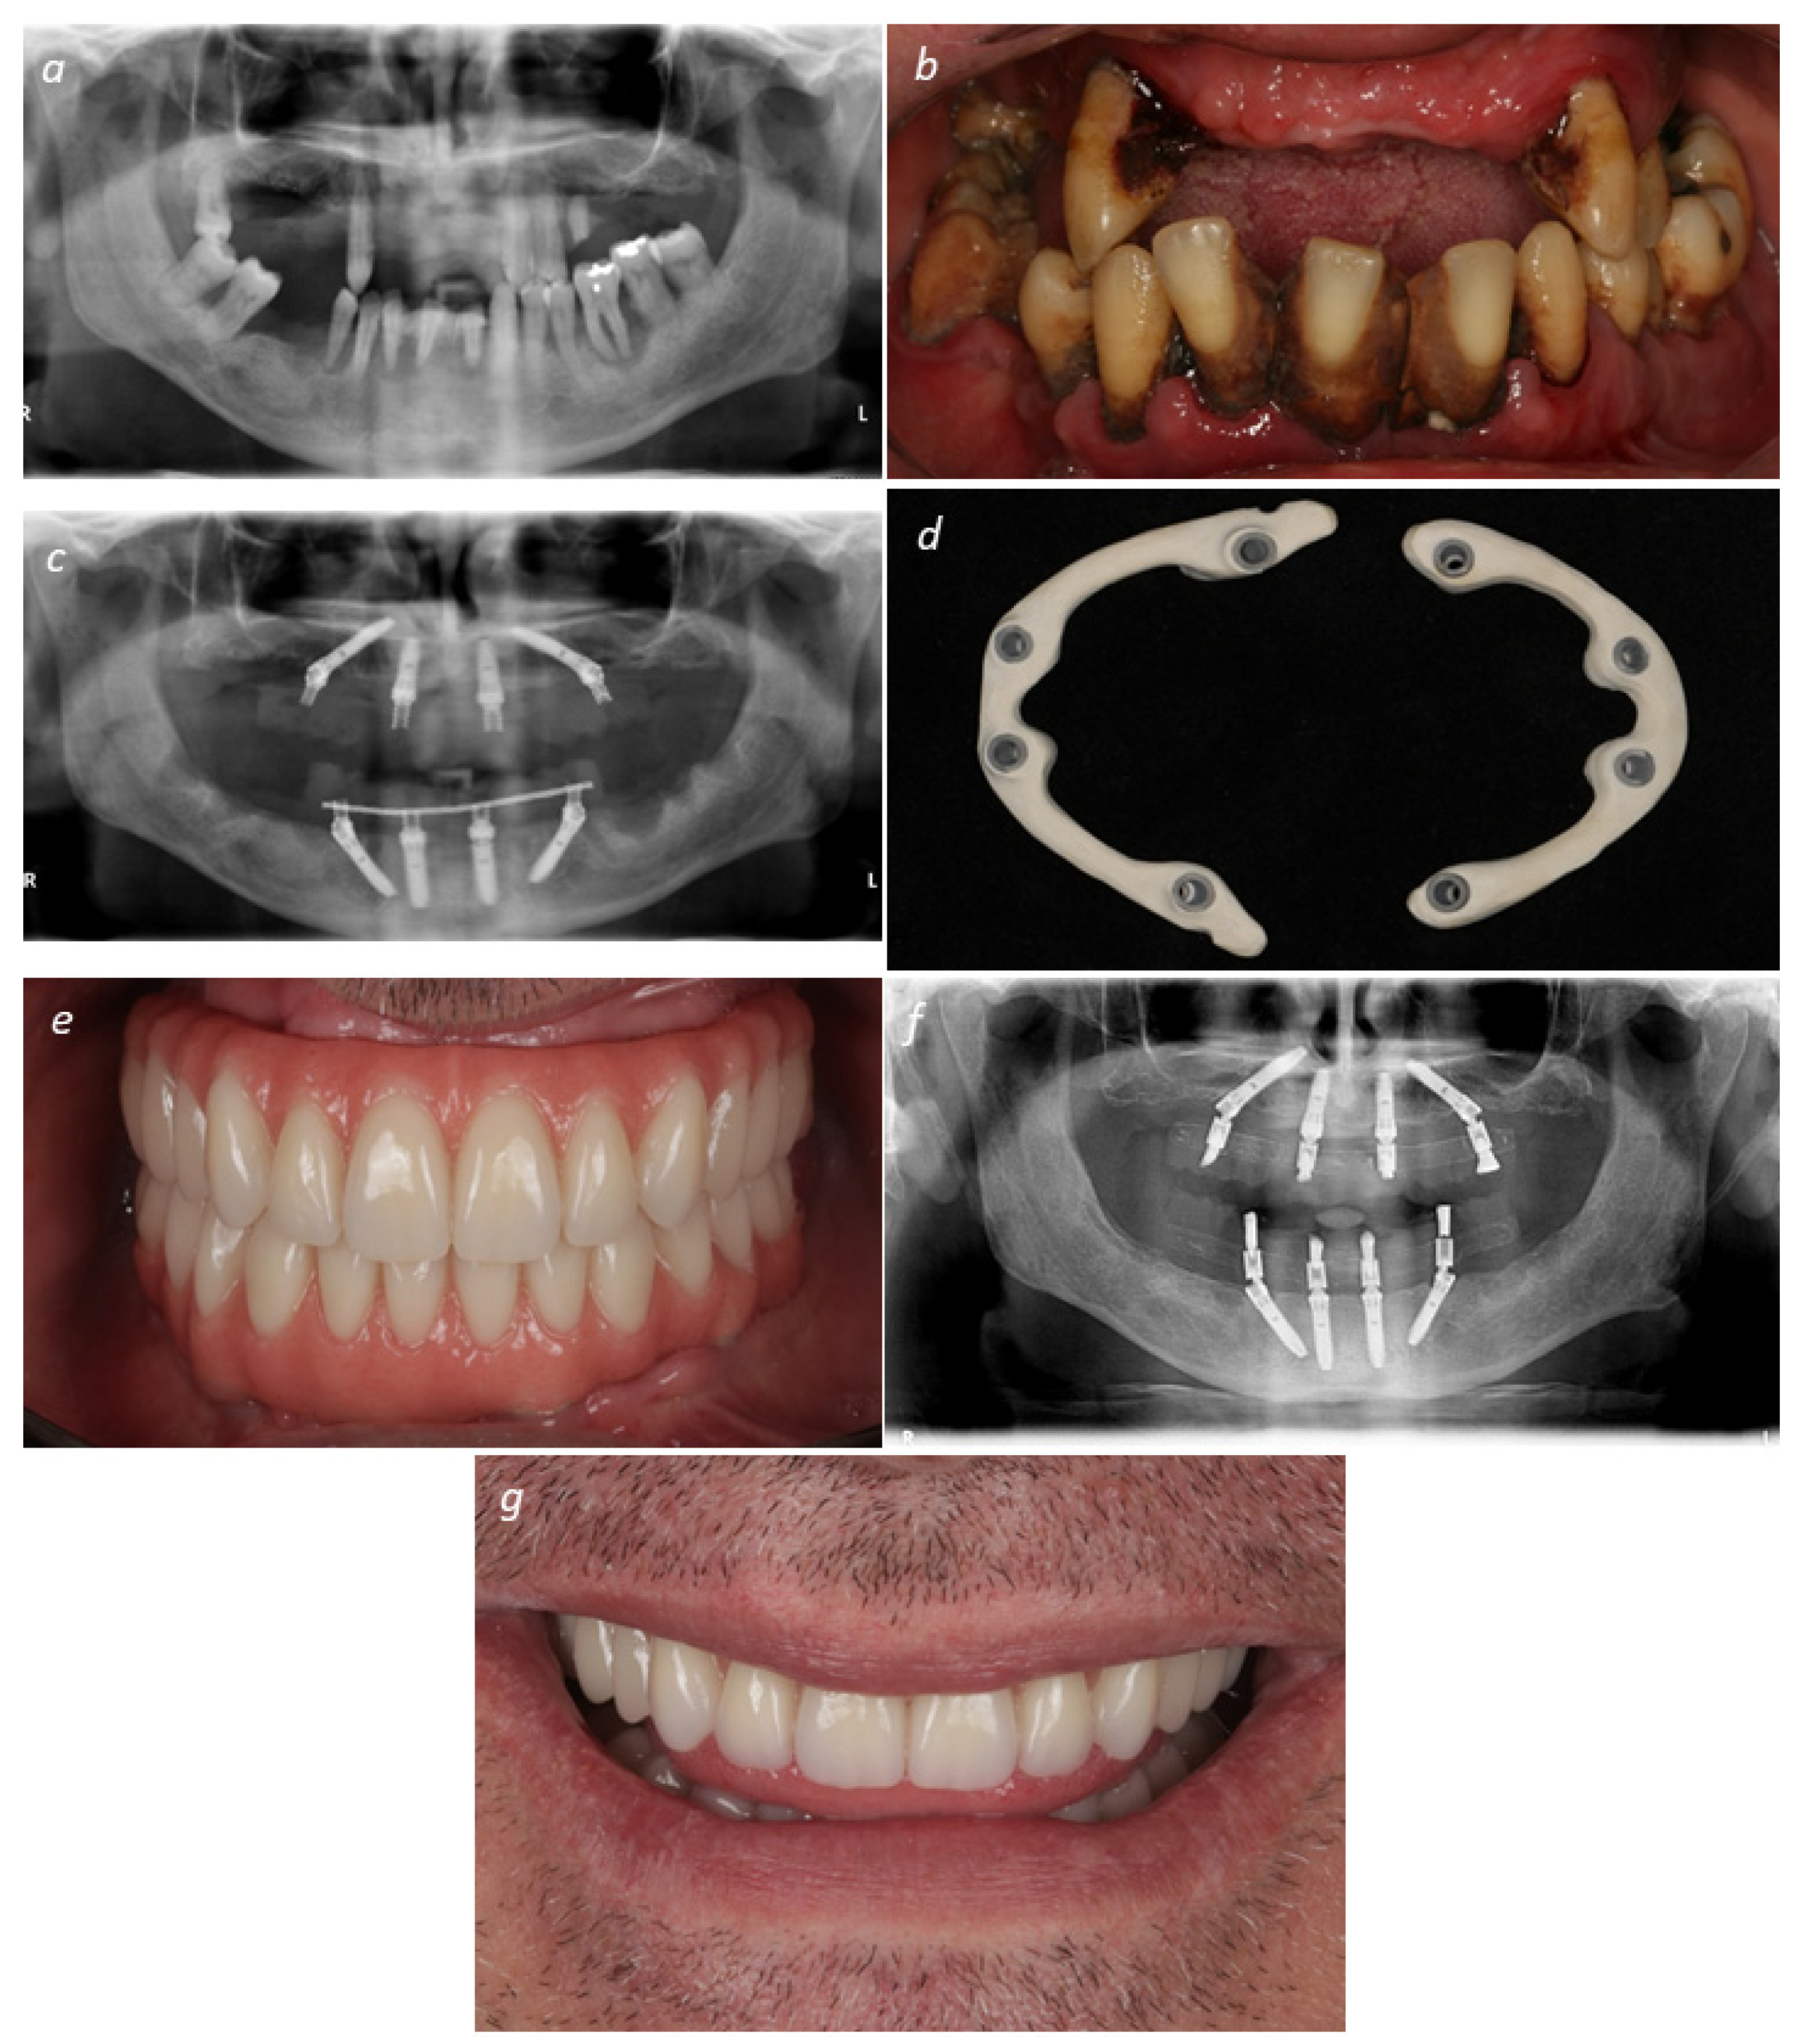

2.2. Surgical and Prosthetic Protocols

2.3. Manufacture and CAD/CAM Guidelines

2.4. Definitive Prosthetic Protocol